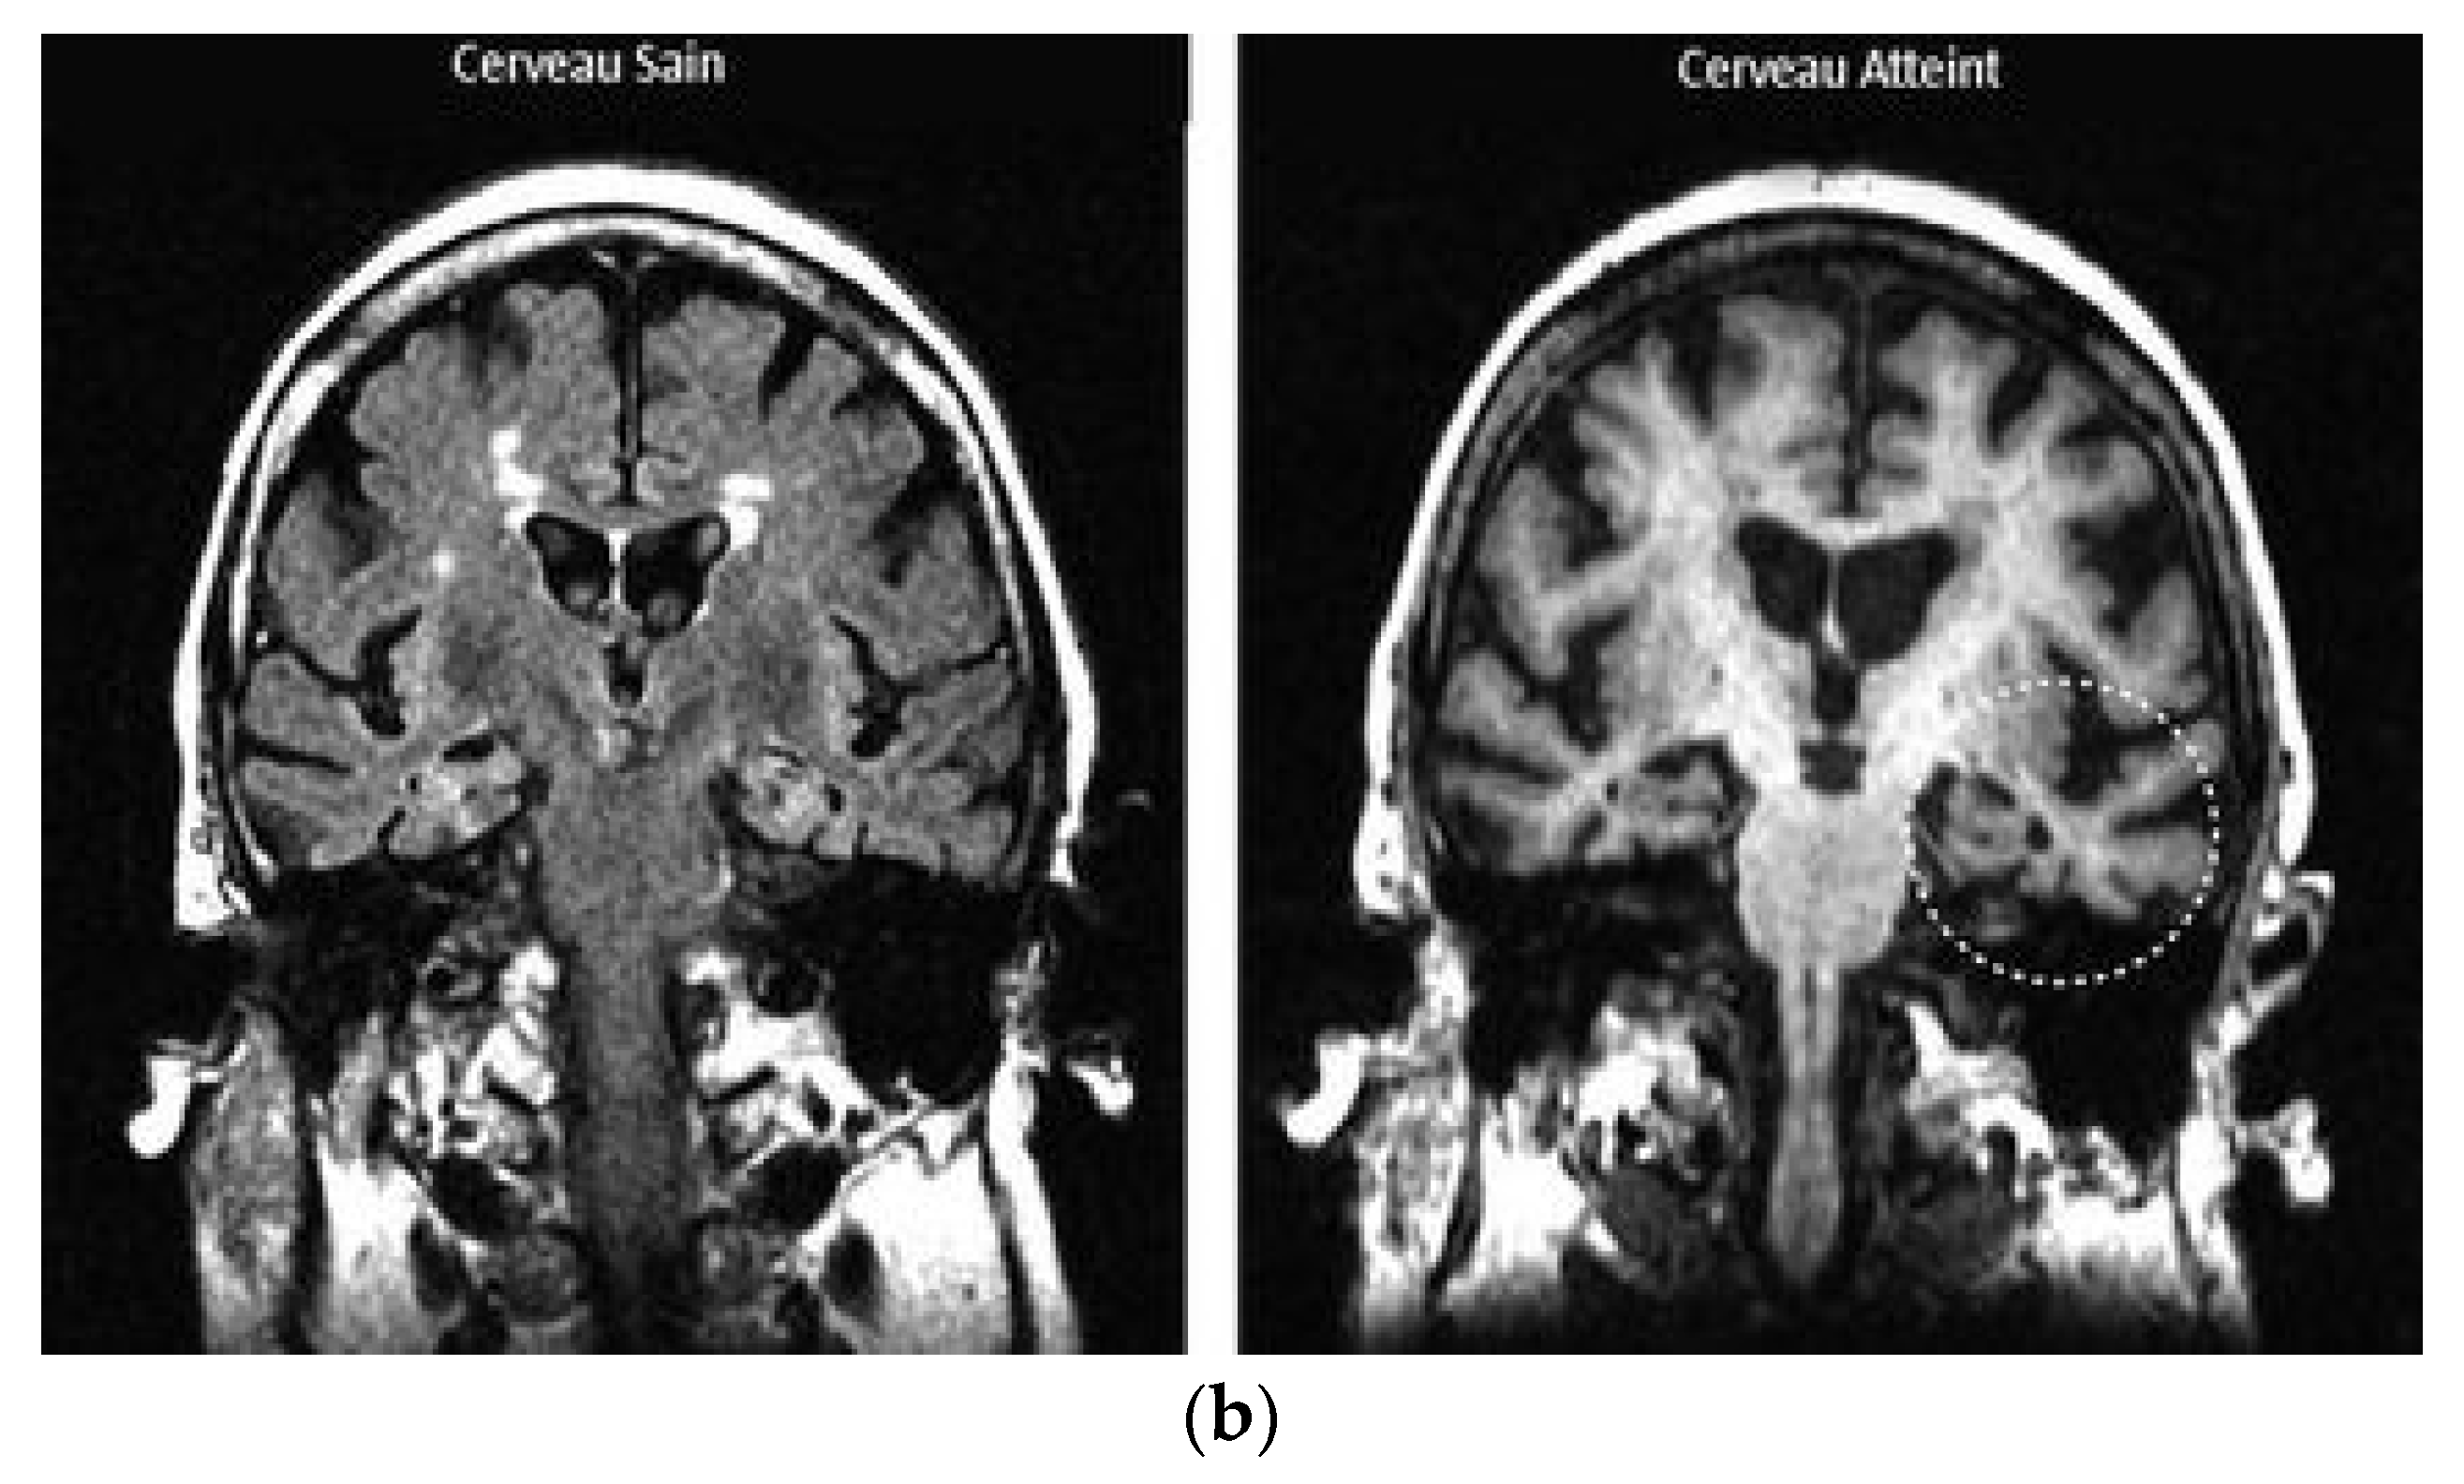

4.4. Application Example